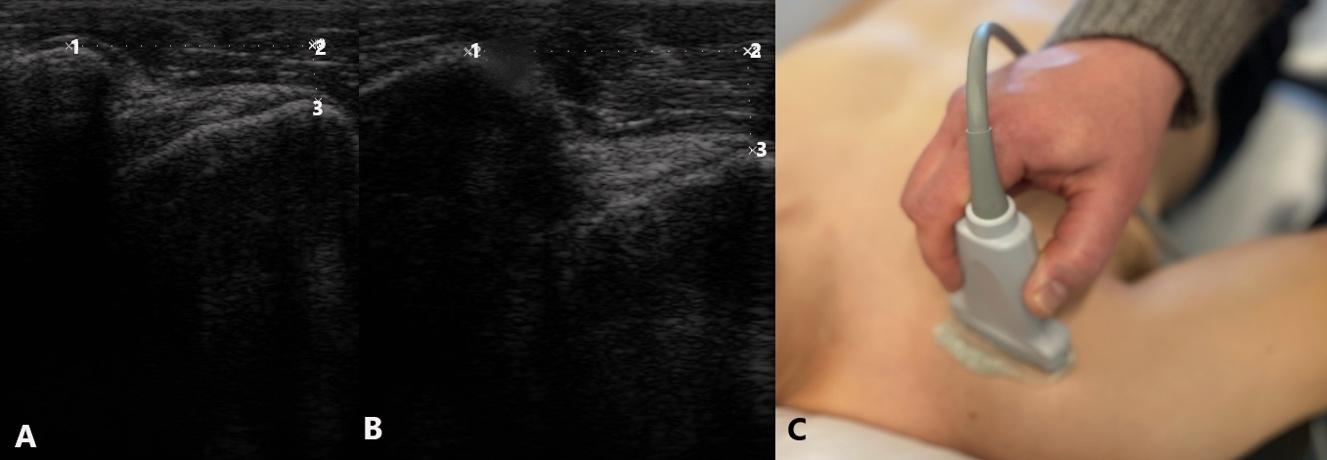

ISOKINETIC TESTING AND INTERPRETATION

Isokinetic testing of the knee flexors and extensors is performed in a seated position using a dynamometer to measure the muscle performance parameters of strength, power, rate of force development, work, and endurance (Figure 3a and 3b). Testing can be performed at multiple angular velocities but is most commonly performed at 180 and 300 degrees/second, as these speeds have been shown to closely approximate functional activity 16,17,28 It is worth mentioning here that one of the persistent criticisms against isokinetics is creating large

Figure 1. Biodex Isokinetic Dynamometer Figure 2. Prototype Small BiodexKnee Isokinetic Dynamometer

Figure 3a. Biodex Isokinetic Dynamometer Figure 3b. Cybex Isokinetic Dynamometer